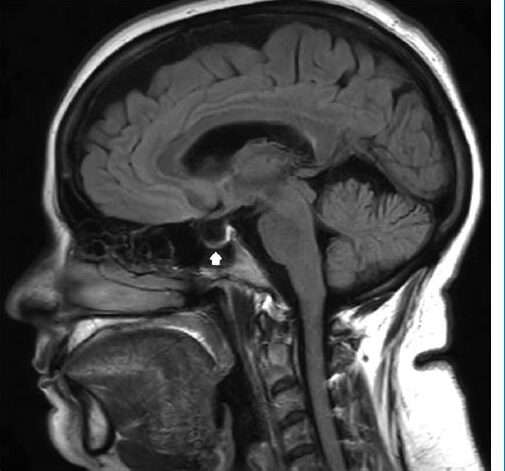

Las investigaciones diagnósticas en pacientes con hipertensión intracraneal idiopática suelen revelar la ausencia de lesiones ocupantes de espacio, lo que implica que no hay masas tumorales ni otras formaciones patológicas dentro del cráneo que compriman el cerebro. El uso de técnicas de imagen como la tomografía computarizada o la resonancia magnética puede mostrar ventrículos cerebrales de tamaño normal o ligeramente reducidos, lo que indica que no hay una expansión significativa del sistema ventricular que sugiera hidrocefalia. En algunos casos, también se observa una silla turca vacía, un hallazgo que refleja la compresión o desaparición de la glándula pituitaria, a menudo asociada con el aumento de la presión intracraneal.

Otro hallazgo característico es la tortuosidad de los nervios ópticos, que se puede observar tanto en la resonancia magnética como en la tomografía computarizada. Esta tortuosidad, junto con la distensión de la vaina del nervio óptico, sugiere que la presión aumentada está afectando la estructura del nervio óptico, lo que contribuye al papiledema y a los trastornos visuales. Además, el aplanamiento del polo posterior del globo ocular es otro signo de hipertensión intracraneal, en el que la presión intracraneal elevada provoca una alteración en la forma del ojo, lo que puede influir en la visión del paciente.